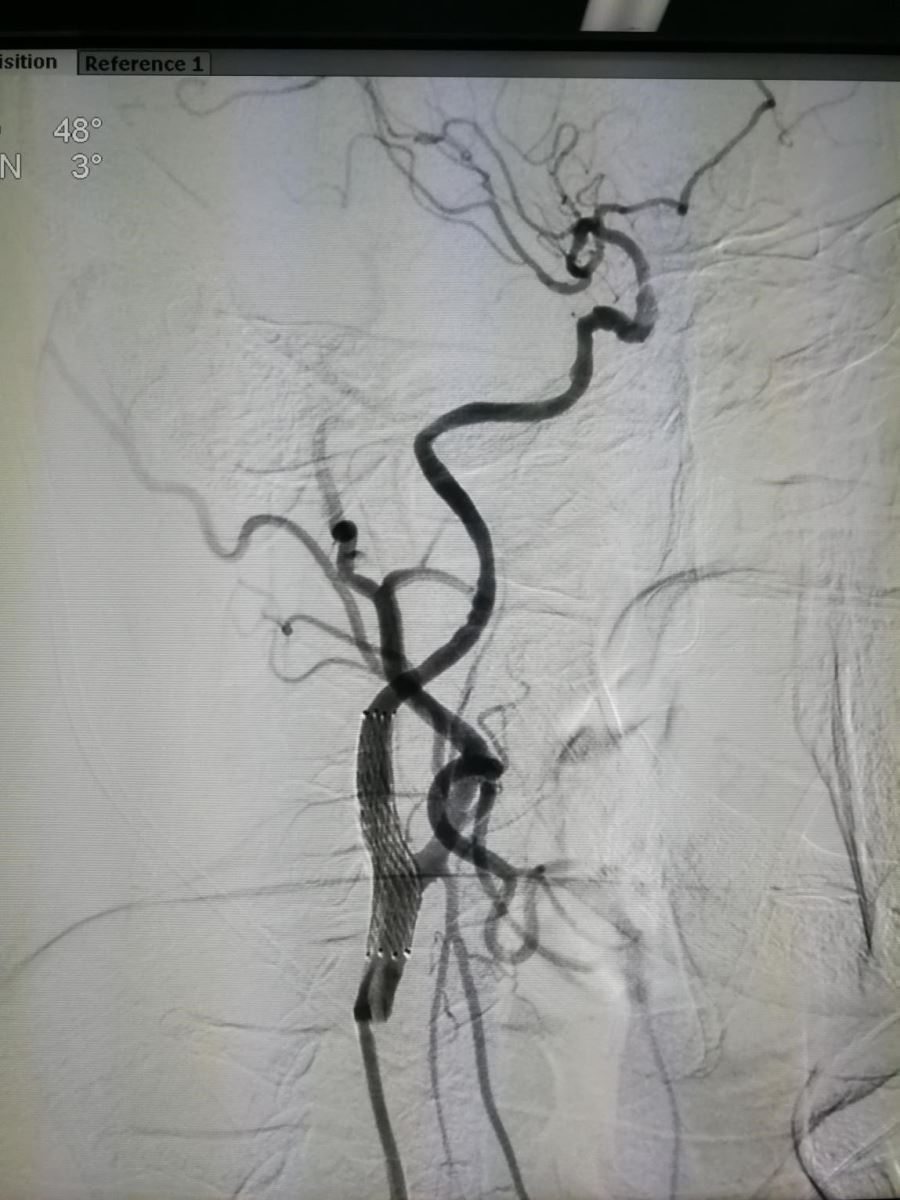

则患者有必要行血管内支架植入治疗(2018-09-12为该患行支架植入治疗)。图4为术后正位,图5为正位支架位置。

.jpg)

图4 图5